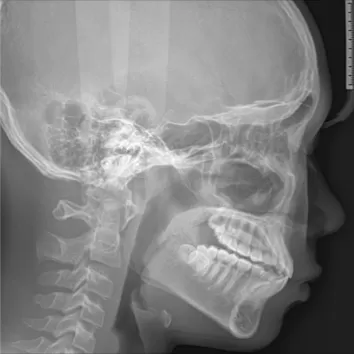

Rayons X avant le traitement

[Radiographie panoramique/Céphalogramme latéral]